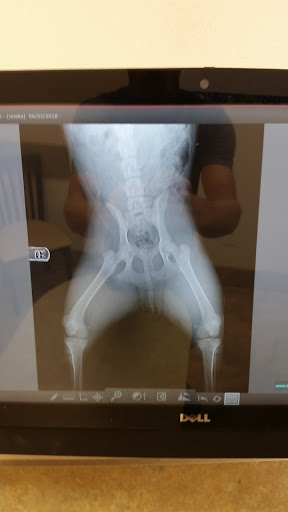

If I didnt have to give them any stars, I wouldnt. We had been going here a few times and they were great. However, they must have new people or have slowly started the "I dont care" moods all around that place. We went in there because it seemed like our dog had a spider bite or something that just would not go away. When the vet took a look at it, she shaved the hair away, pricked it a few times with the needle to get a culture of it, and told us that basically it was an abscess that she wanted to get off as soon as she can because it looked like some type of skin cancer that was starting. So since my dog is like my child, I said go ahead but we needed to talk about payment plans since we were moving from Phoenix to Eugene, OR. They told me that there would be a $50 down payment with a $15 service charge. Completely understandable and definitely affordable, they just wanted it paid off in a year which wasnt going to be a problem at all. We went in for the surgery and all of sudden they wanted half or 3/4 of the payment. When I told them what was told to us, they thought they could bluff me into paying it. At that point I even called my husband to make sure I didnt misunderstand what was originally told to us. So I said no I only had what they had originally told me. Then the vet said oh dont worry its not an emergency at all. So I walked out very mad because on top of all that, the prescription they gave to me for my dog hip dysplaysia was for the completely wrong dog with a lot of its owners information on, and when I got the new one it was the wrong dosage. To put the cherry on top it has been a week since the vet visit and my dog is now sitting here with this lump double the size and it just ruptured. To say these people are unprofessional is an understatement. They just dont care.